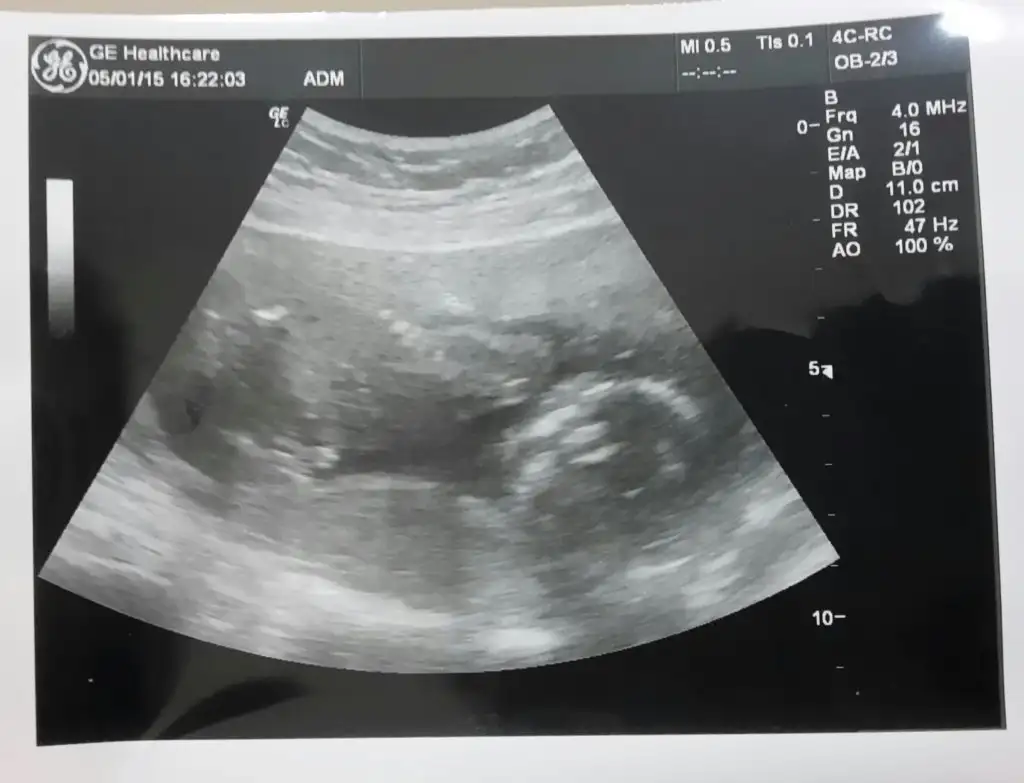

Bayanlar benimkinede yorum yapabilir misiniz

Geri dönüşler bekliyoruz arkadaşlar sizlerden bu arada yorum yapmadigim iki arkadaş var sizinkilerin nublarini göremedim başka pozlariniz varsa ekleyin